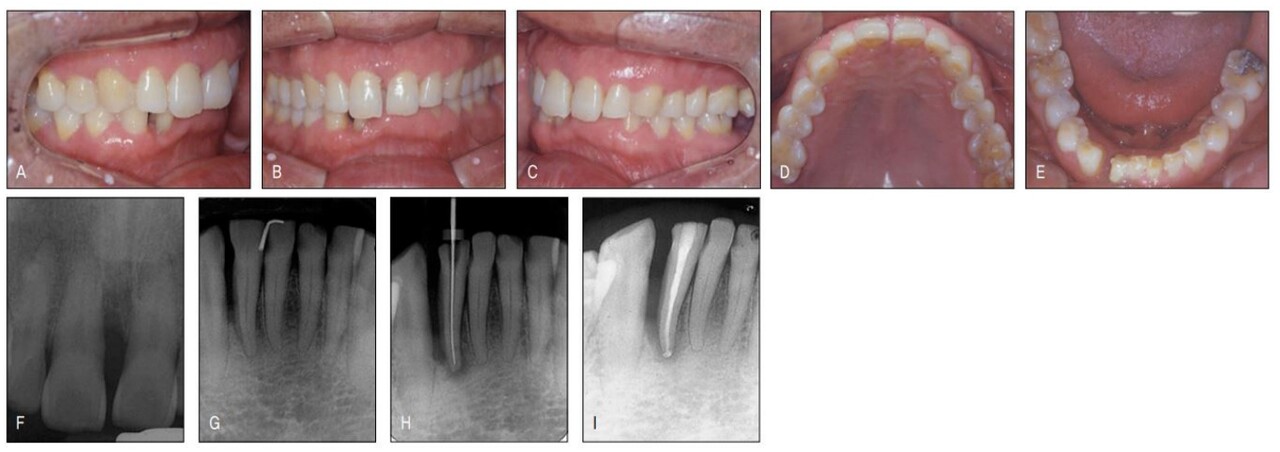

지난 일년 전 하악우측 측절치의 치주 및 근관치료 중 갑작스럽게 치아가 전위되면서 원심부에 공간이 발생한 환자로, 보철을 위해서는 공간재분배가 불가피하여 교정 치료를 위해 의뢰된 환자였다. 하전치부는 교모와 함께 정출이 나타나 이론적으로는 intrusion 후 보철이 필요하지만 환자는 공간재분배라는 간단한 교정치료 조차 받기를 주저할 정도이어 치료계획에 넣지도 않았다.

하악의 공간외에 상악정중부에도 치주질환으로 인한 공간이 있어 치료시 하악 상악같이 할 것을 권유하였으나 환자는 보철을 위해 꼭 필요한 하악에서의 교정만 하는 것으로 하고 상악 치료는 거부하였다. 후에 알게 된 사실이지만 환자가 상악교정을 거부한 이유는 장치의 노출 때문이었다. 교정 장치가 보기 싫어서가 아니라 “나이 들어서 교정치료를 받는 것이 민망해서”라고 하였다. 아직도 많은 이들이 교정은 심미목적으로만 치료받는 것으로 잘 못 알고 있고, 이에 대한 계몽이 필요하다는 것을 본 증례가 여실히 보여주었다.

과개교합으로 인해 순측부착이 불가하여 설측으로 장치를 부착하였더니 보이지 않는 장치라 환자가 매우 좋아하였다. 한 개의 와이어를 사용하여 간단히 하악교정을 한 후 환자에게 다시 상악 교정을 권유하였더니 환자는 흔쾌하게 상악도 교정을 하겠다고 하였다. 하악에서처럼 심미적 교정장치로 치료 받을 수 있을 것으로 기대했기 때문이었다.

그러나 전치부 과개교합으로 상악설측면에서의 장치 부착이 불가하여 환자에게 투명교정장치를 설명하였고 이 역시 심미적 장치이어 환자가 수락하고 투명교정장치로 간단하게 공간클로져 교정을 시행 하였다. 가철식 장치이어서 다소의 경사이동이 발생하였고 치주질 환으로 우측의 중절치가 더 정출하여 비심미적인 절단연이었으나 스트리핑 그리고 re-shaping 등을 이용하여 심미적인 절단연을 만들어주었다. 교정을 주저하였던 환자는 설측및 투명장치 등 심미적 장치로 인해 교정치료 내내 크게 만족해 하였다(그림 23-7~10).